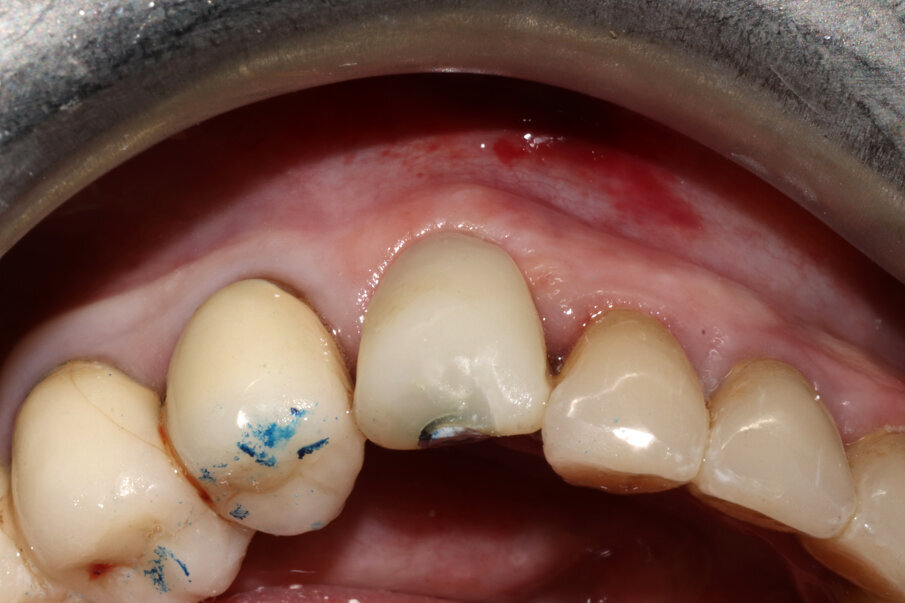

Fig. 3_Il caso clinico descritto: elemento 3.3 già rivestito di corona protesica, vitale e dolente.

Figg. 9-11_Inserimento dell’impianto e costruzione di una corona provvisoria. Si noti la forma a “C” dello shield e, al termine dell’intervento, la compostezza dei tessuti, gestiti senza alcun tipo di lembo.